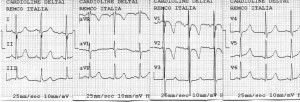

Evoluţia imediat postoperatorie a fost fără complicaţii, sugarul revenind în secţia de cardiologie pentru recuperare. Condiţiile generale erau ameliorate, notându-se chiar şi o uşoară creştere ponderală. Controalele ecocardiografice succesive au evidenţiat însă o dilataţie graduală a ventriculului stâng cu afectarea progresivă a funcţiei sistolice şi apariţia ulterioară a unei insuficienţe mitrale severe. Nu a putut fi vizualizată originea arterei coronare stângi din aortă, în plus notându-se flux bidirecţional în artera coronară descendentă anterioară la examenul Doppler color, ridicând suspiciunea de origine anormală a arterei coronare stângi (Figura 3). Presiunea pulmonară se redusese semnificativ (presiunea pulmonară medie a scăzut de la 40 mmHg la 21 mmHg), iar la nivelul septului interatrial nu exista şunt rezidual. Electrocardiograma evidenţia semne de ischemie miocardică, inexistente pe electrocardiogramele de dinainte de intervenţie: segment ST subdenivelat descendent în precordialele stângi şi unde T negative simetrice în precordialele drepte (Figura 4).

Figura 4. Electrocardiogramă: segment ST subdenivelat descendent în precordialele stângi şi unde T negative simetrice în precordialele drepte.

În aceste condiţii sugarul a fost din nou transferat în serviciul de chirurgie cardiacă. S-a realizat cateterismul cardiac care a confirmat suspiciunea ecocardiografică de origine anormală a arterei coronare stângi din artera pulmonară (Figura 5). S-a reintervenit chirurgical. Intraoperator s-a observat originea arterei coronare stângi la nivelul bifurcaţiei arterei pulmonare, posterior, având un trunchi comun destul de lung. S-a realizat implantarea arterei coronare stângi în aortă. Evoluţia post-reintervenţie a fost bună, cu instalarea unei bune creşteri ponderale ulterior. Ecocardiografia a ilustrat noua origine a arterei coronare stângi din aortă (Figura 6), absenţa şuntului la nivelul septului interatrial şi ventriculul stâng revenit la o contractilitate bună (Figura 7); insuficienţa mitrală era uşoara şi persista defectul septal interventricular muscular apical mic. Electrocardiograma s-a normalizat (Figura 8). La 3 ani de la intervenţie copilul este asimptomatic şi are o dezvoltare psihosomatică corespunzătoare vârstei.

Figura 9. Electrocardiogramă: ritm sinusal 103/minut, fără modificări patologice de repolarizare.